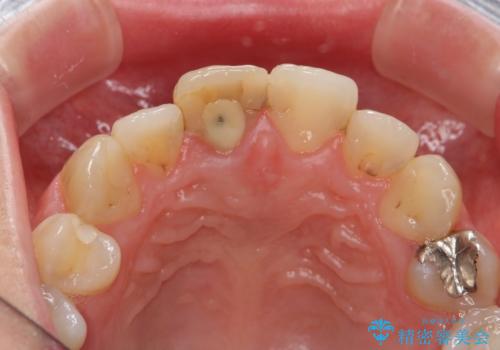

- 「 以前神経を取った歯の変色が気になる。前歯をきれいにして欲しい。」と治療を希望され来院されました。

目立つ上顎前歯に変色・大きな虫歯治療痕が見られ、審美障害を引き起こしています。